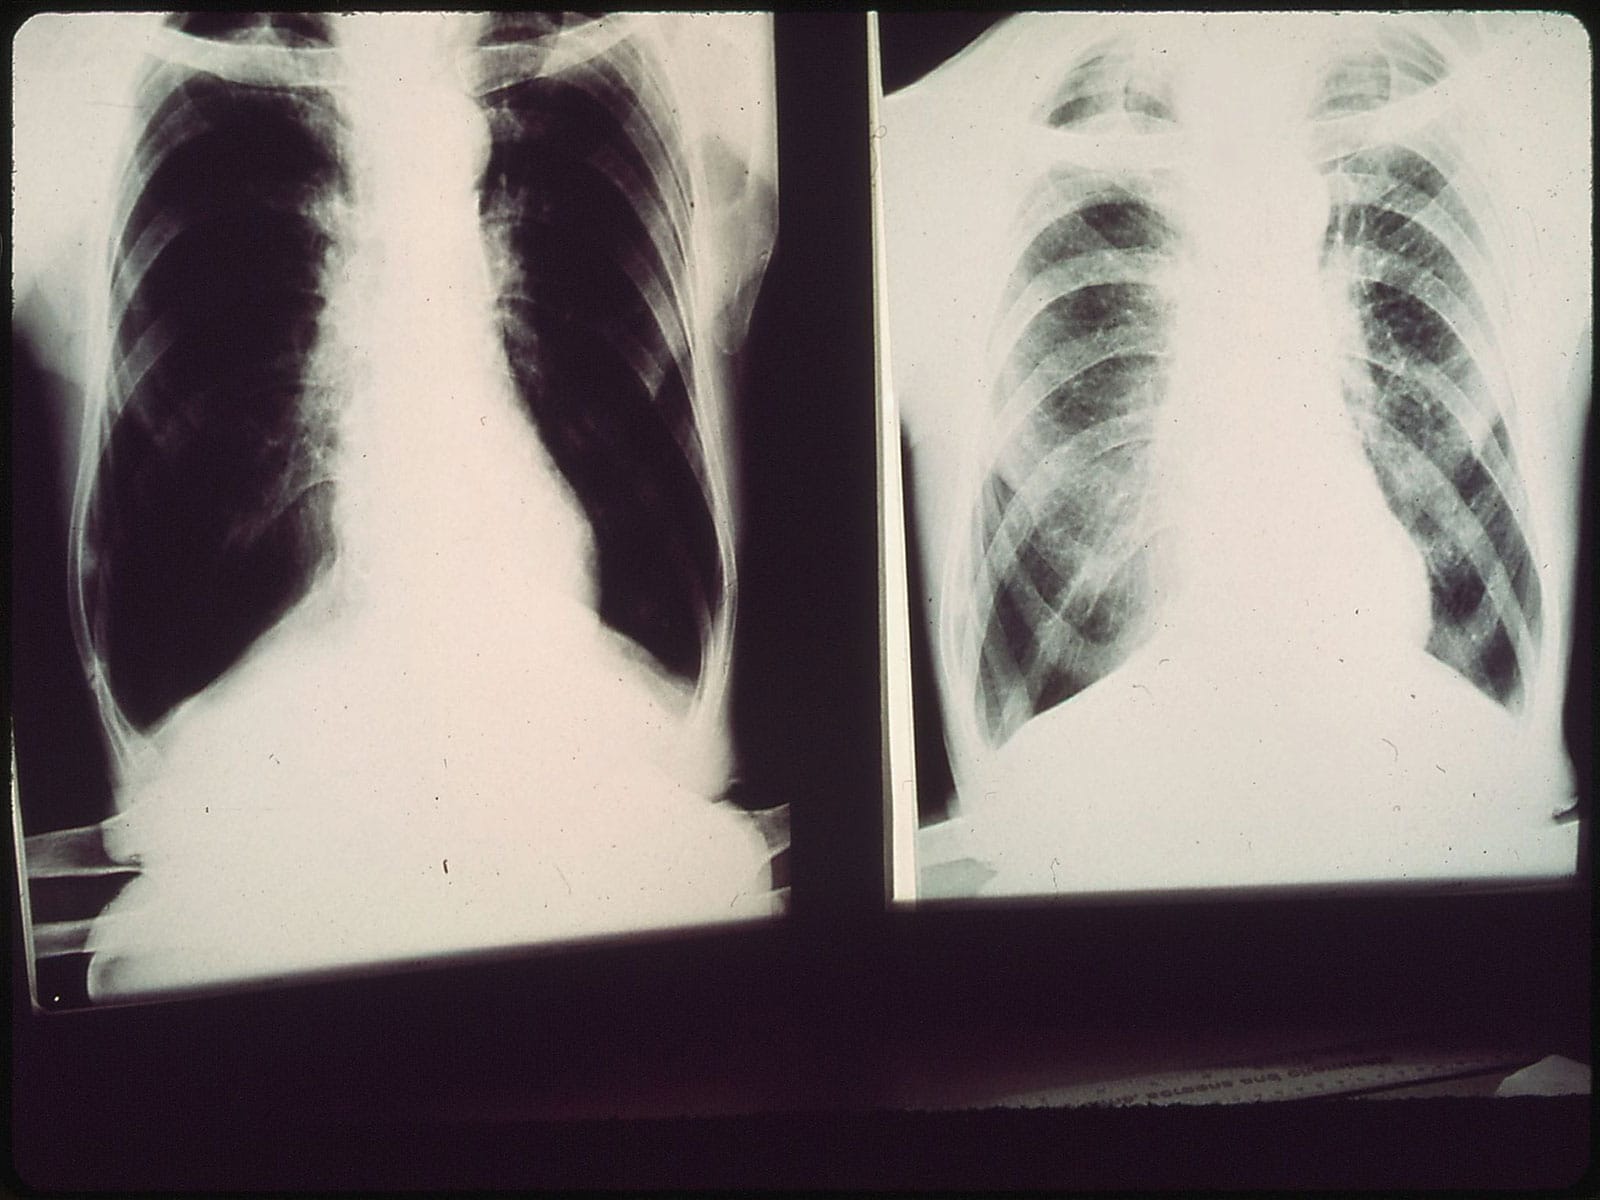

Testiranje će se održati u okviru Svetskog dana borbe protiv hronične opstruktivne bolesti pluća (HOBP) pod sloganom “Nije prekasno” kako bi se edukacijom stanovništva povećala svest o prevenciji i pravilnom lečenju ove bolesti.

HOBP se uglavnom javlja kao posledica dugogodišnjeg pušenja, a veliki broj ljudi nije ni svestan da je već oboleo.

Bolest se razvija polako, tokom više godina, čak i decenija, a odlikuju je otežano disanje, zamaranje pri obavljanju uobičajenih aktivnosti, hronični kašalj – navode u Zavodu.

Simptomi hronične opstruktivne bolesti pluća, kako navode, mogu biti kašalj koji ne prolazi, iskašljavanje šlajma i sluzi, ostajanje bez daha i zamaranje pri svakodnevnim i jednostavnim fizičkim aktivnostima kao što su penjanje uz stepenice, šetnja, odlazak u kupovinu, kupanje i oblačenje.